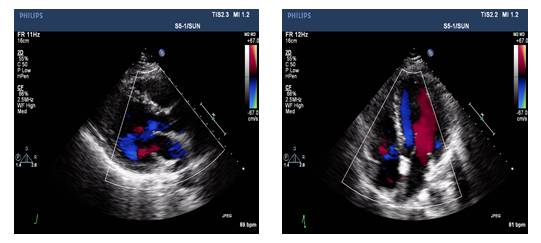

UCG(2014-5-14):

◆IVS 0.86cm, LVDd 6.4cm, EF 40%

◆轻-中度二尖瓣关闭不全

◆UCG: LVDd 5.7cm, LAD3.9cm, LVEF 50%, 轻中度二闭

◆UCG: LVDd 5.6cm, LVEF 53%

◆UCG: LVDd 5.65cm, LAD3.9cm, LVEF: 50%